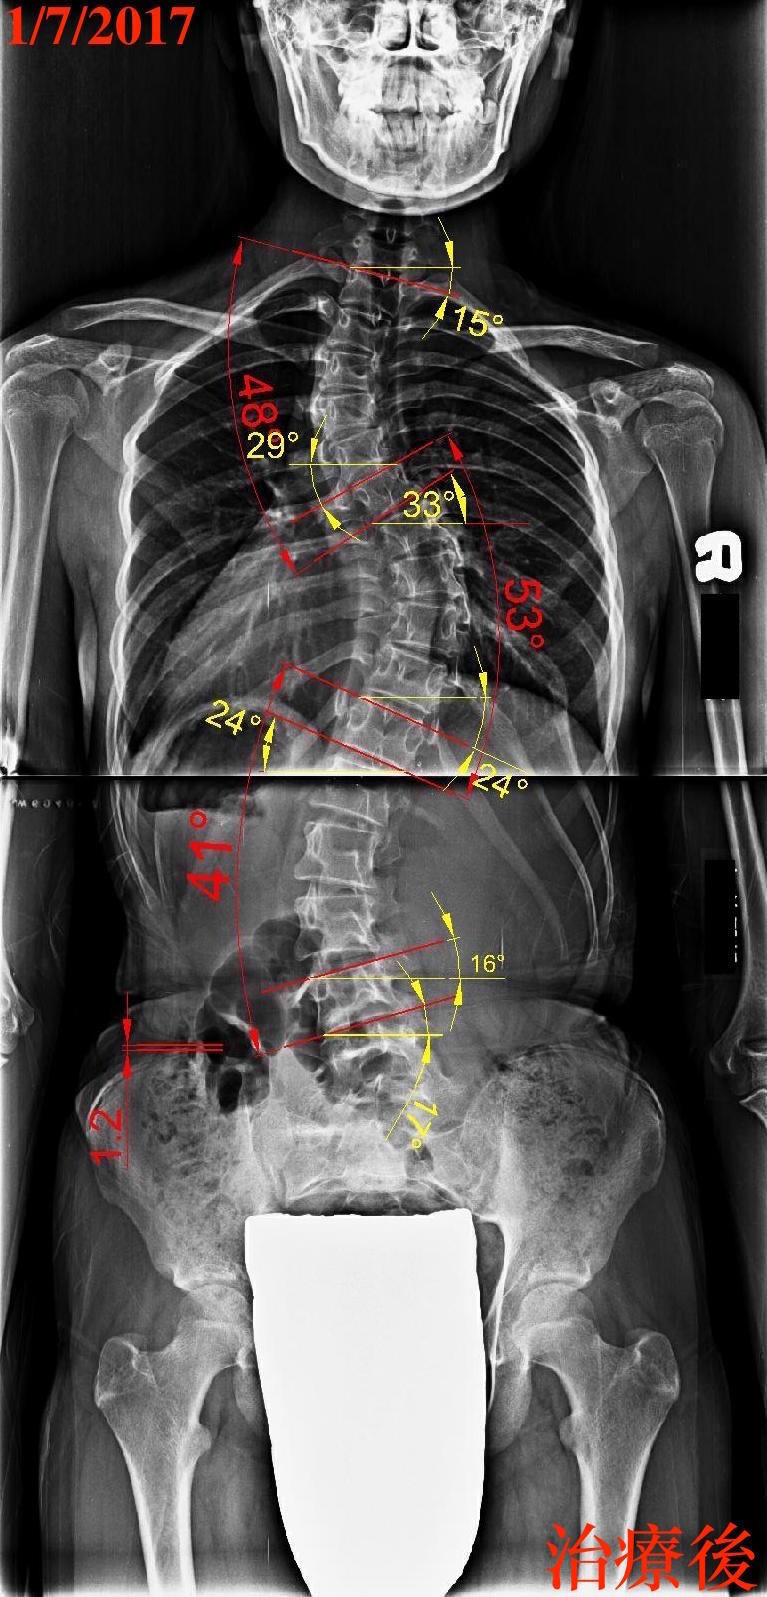

下面2張圖是同一個個案在治療前後的X光片,這個個案的主要彎度在中段胸椎,但她的上胸椎已經有彎向左側的傾向(藍頭箭頭處),而這個個案曾經接受過背架的矯正治療,為了要矯正主要彎度,所以過度向上推擠左側肩膀,導致上胸椎的彎度變得更加明顯(下圖右),所以為了讓主彎進步6度(59度~53度),使得上胸椎惡化5度(43度~48度),進步及惡化的幅度相當接近,所以實際上只是把主要彎度的問題推給上胸椎,而且造成體態外觀變得更加不對稱(左肩明顯變高、頭部更加偏向右側),這樣會使得未來要改善這個案的側彎度數變得非常困難(請參考”脊椎側彎背架的迷思!迷失?-上”、”閻曉華說脊椎側彎第九章 脊椎側彎背架的真相)。